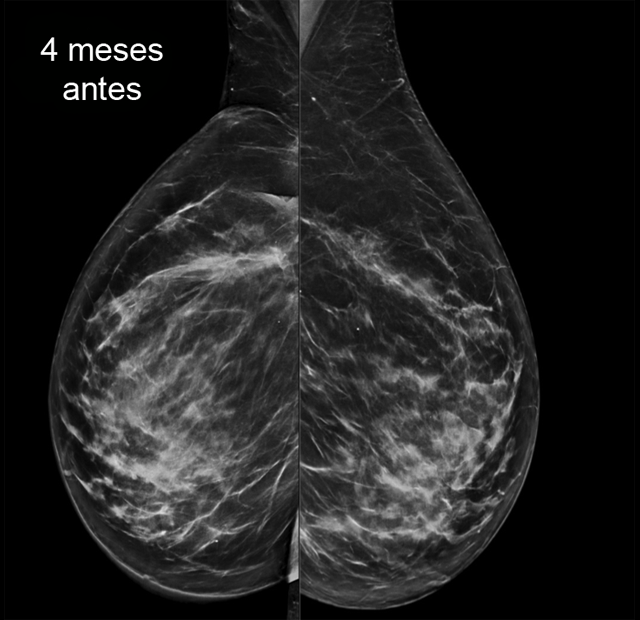

Último control mamográfico hace 4 meses estable.

1. ¿Cuál sería tu informe radiológico de la mamografía y ecografía y qué recomendarías?

- D. Cambios morfológicos en MD en relación con sus antecedentes, con engrosamiento cutáneo en CCII de MD de nueva aparición (BI RADS 4). Se recomienda biopsia cutánea (punch).